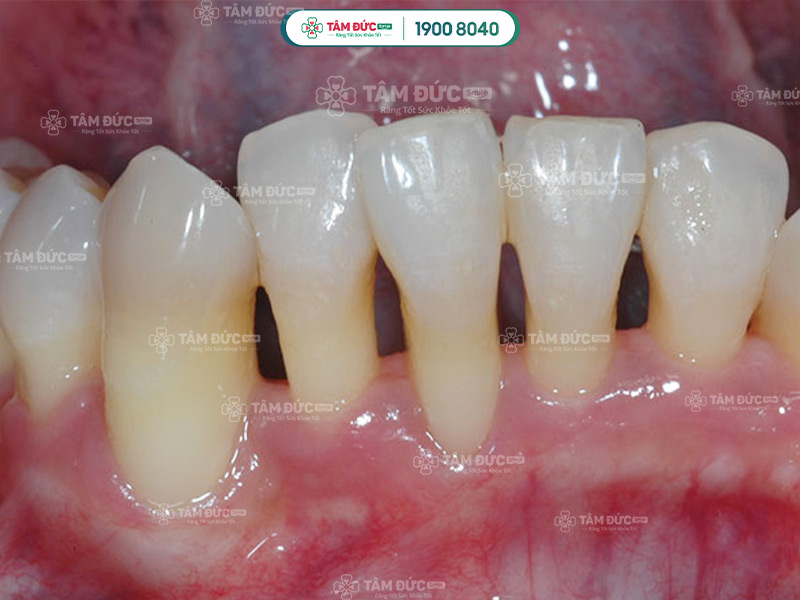

Cao răng dày đặc là nguyên nhân làm viêm nướu và gây tụt lợi nhanh chóng

Các bác sĩ đã xác định rằng: Tụt lợi chân răng là vấn đề nguy hiểm, Quý khách không nên chủ quan. Tụt lợi chân răng thường xảy ra ở răng nanh hàm dưới. Nếu tụt lợi xuất hiện ở răng cửa hoặc răng hàm, điều đó chứng tỏ bệnh lý đã bước sang giai đoạn nghiêm trọng.

Khi bị tụt lợi, chân răng mất đi lớp đệm bảo vệ, từ đó, men răng dễ bị ăn mòn bởi môi trường bên trong khoang miệng. Về lâu dài, tụt lợi sẽ làm ảnh hưởng mạch quản và hệ thống dây thần kinh xung quanh răng.

3.3. Làm cho răng trông dài hơn

Vùng lợi xung quanh bị tụt xuống sẽ làm cho thân răng trồng dài hơn. Răng nhạy cảm rất dễ bị bám màu hoặc tạo thành kẽ hở lớn với răng còn lại. Điều này sẽ làm ảnh hưởng nghiêm trọng đến thẩm mỹ nụ cười.

Răng có vẻ dài hơn khi Quý khách bị tụt lợi chân răng